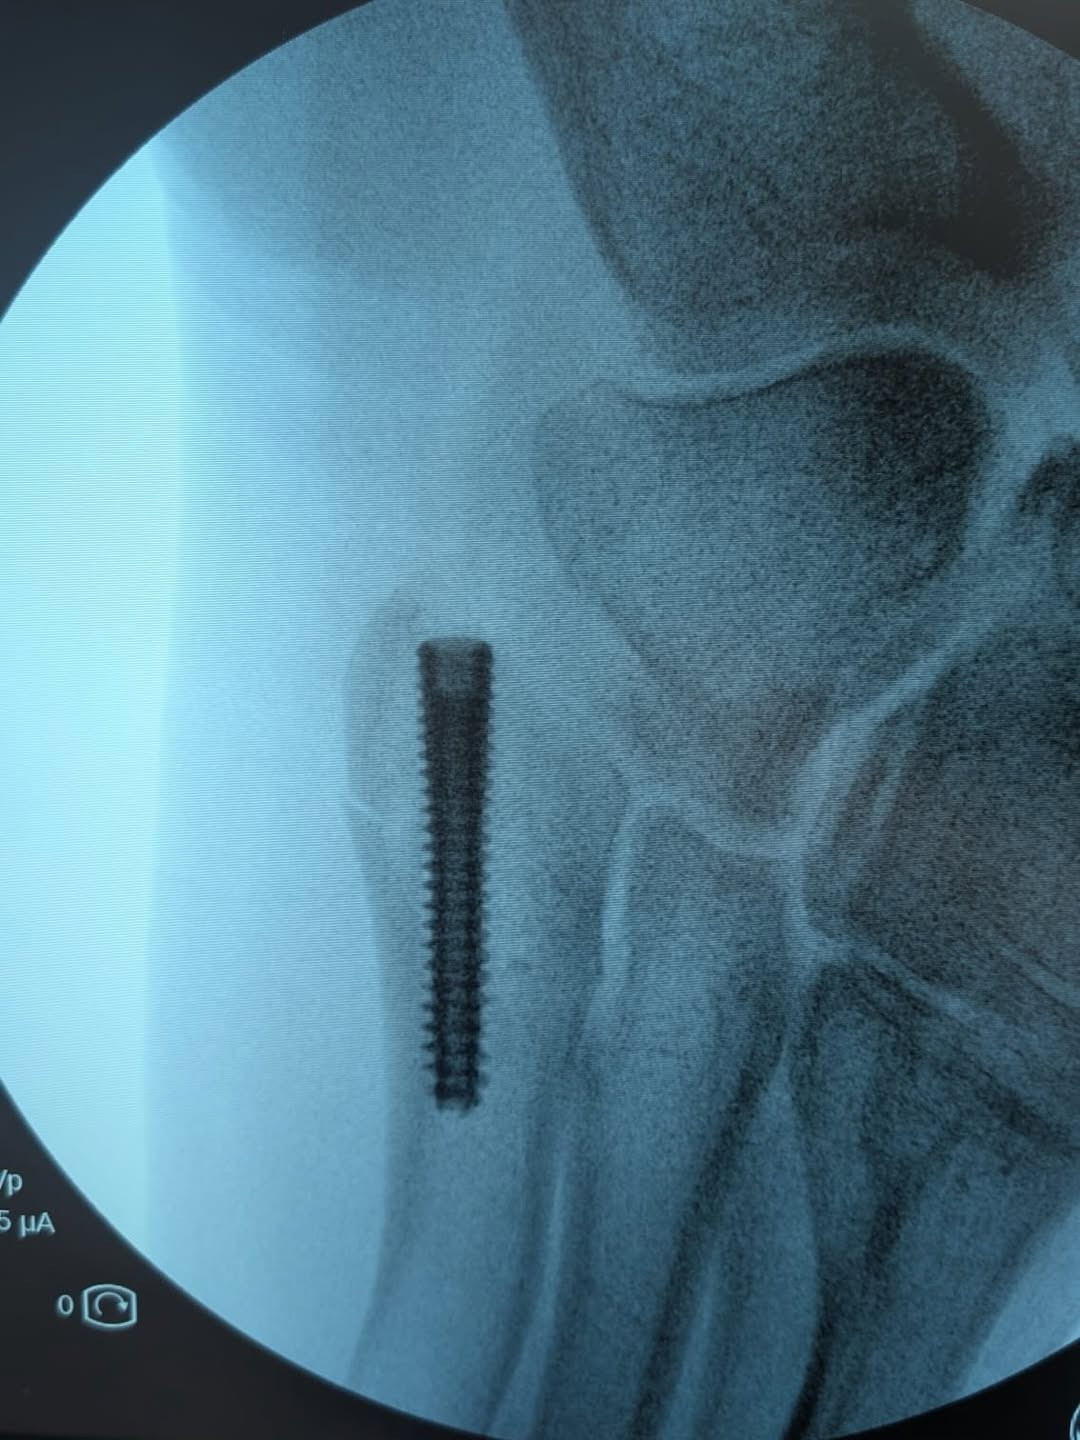

Hanya 10 hari dari insiden kecelakan di Mol, Wout van Aert sudah kembali berlatih di jalanan. Terlihat normal. Akan tapi, di hari ia mengalami insiden, Van Aert harus menjalani prosedur operasi. Ini karena pergelangan kakinya mengalami retak. Sebuah pen pun harus dipasangkan di pergelangan kakinya.

Pen terpasang di pergelangan kaki usai insiden di Mol.